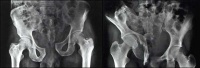

(1)骨盆后前位X线片:X线平片检查一般可明确骨折部位骨折类型及其移位情况,亦常能提示可能发生鵻的并发症。全骨盆后前位X线片可显示骨盆全貌对疑有骨盆骨折者应常规拍摄全骨盆后前位X线片以防漏诊对骨盆后前位X线片上显示有骨盆环骨折者,为明确了解骨折移位情况还应再摄骨盆入口位和出口位片。(2)骨盆入口位片:患者仰卧,X射线从颅侧投向尾侧,与片盒成60°倾斜摄片本位片可显示耻骨段骨折移位;骨盆向内、向外旋转和向内移位的程度;骶髂关节向后移位及骶骨骨折是否侵犯椎管;同样可显示坐骨棘撕脱骨折。

(3)骨盆出口位片:X线是从尾侧投向颅侧,与片盒成45°角本片可显示桶柄型损伤与耻骨体骨折,对确定半骨盆有无向上旋转移位是很有用的,在本片上同样可显示骶骨或髂骨骨折移位情况。

CT检查对骨盆骨折虽不属常规但它可在多个平面上清晰显示骶髂关节及其周围骨折或髋臼骨折的移位情况,因此凡涉及后环和髋臼的骨折应行CT检查骨盆三维重建CT或螺旋CT检查更能从整体显示骨盆损伤后的全貌,对指导骨折治疗颇有助益但应铭记对血流动力学鵻不稳定和多发伤患者,后前位全骨盆X线片是最基本和最重要鵻的放射学检查不要在拍摄特殊X线片上花费时间,更为重要的是尽快复苏。